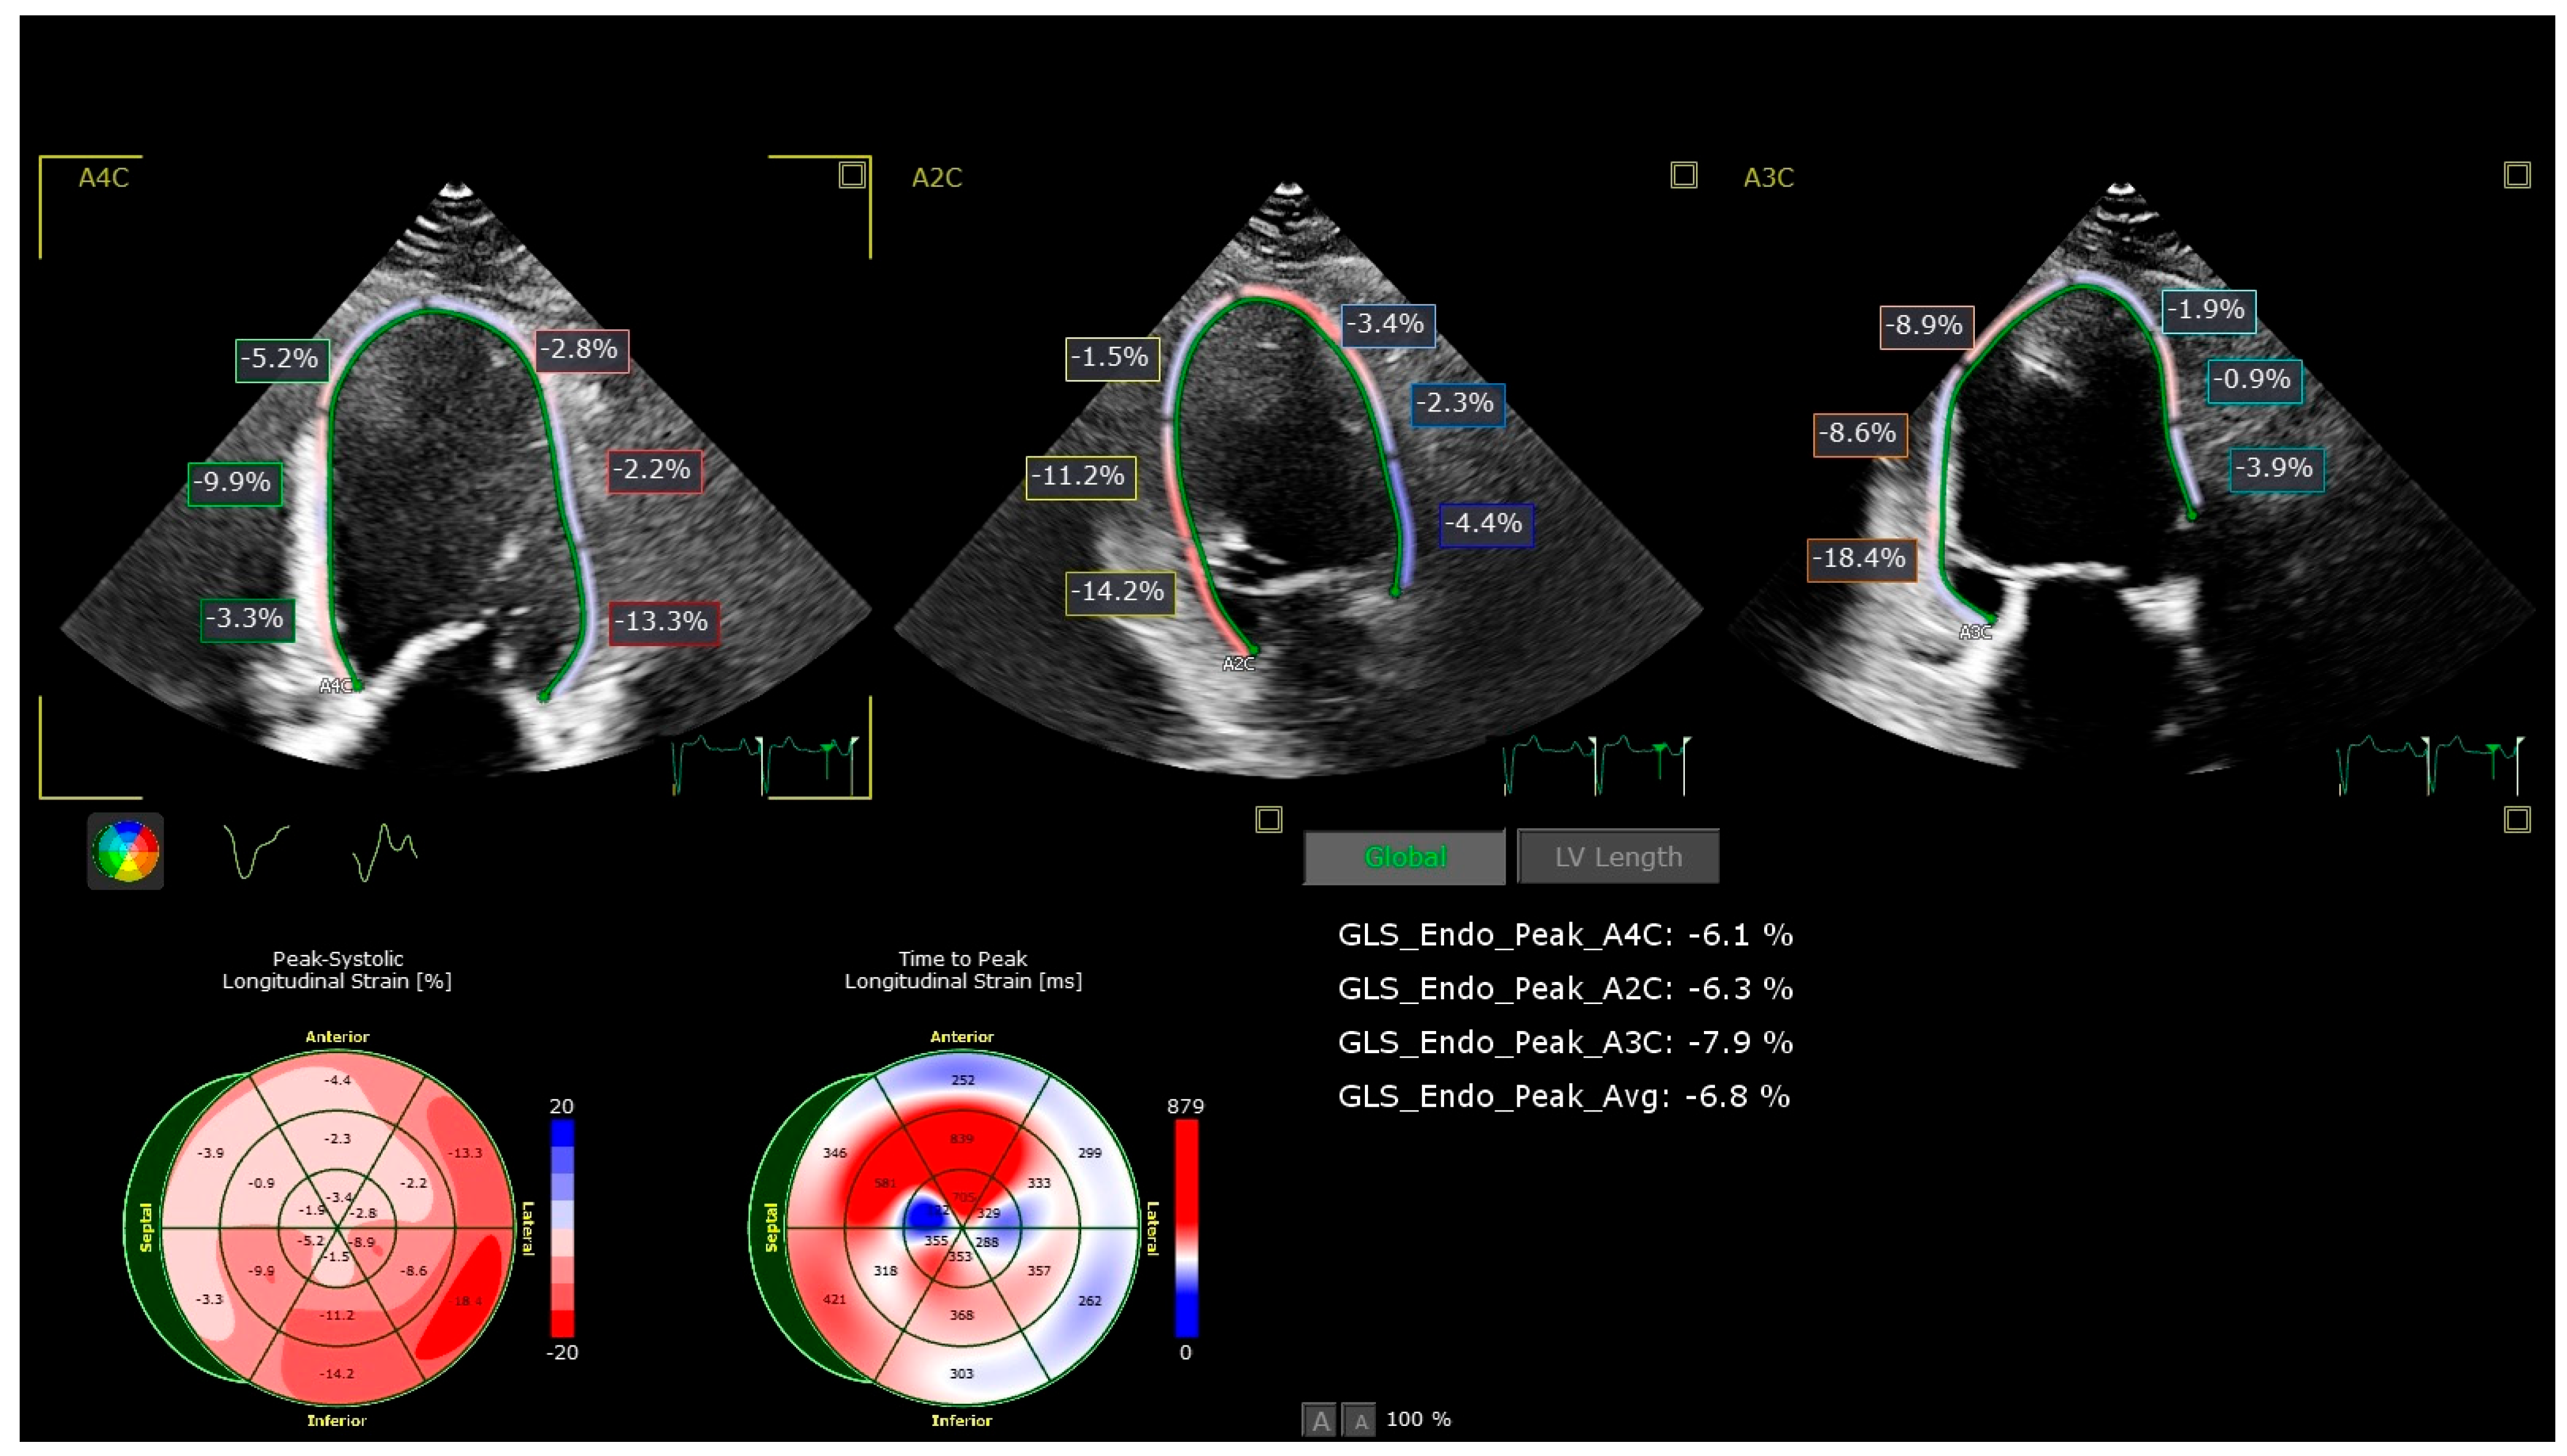

- Global longitudinal strain (GLS): Assessed by 2D speckle-tracking echocardiography using apical views (four-chamber, two-chamber, and long-axis). The endocardial border was manually traced, and tracking was automatically performed, with manual adjustments as necessary. A GLS value less negative than −19% (i.e., >−19%) was considered abnormal based on vendor-specific reference ranges.

| GLS, % | −20.5 ± 1.8 | −19.0 ± 2.0 | −17.5 ± 2.2 | −16.8 ± 2.4 | <0.001 |

| Abnormal GLS (<−19%), n (%) | 8 (13.3) | 28 (35.0) | 50 (62.5) | 55 (68.8) | <0.001 |